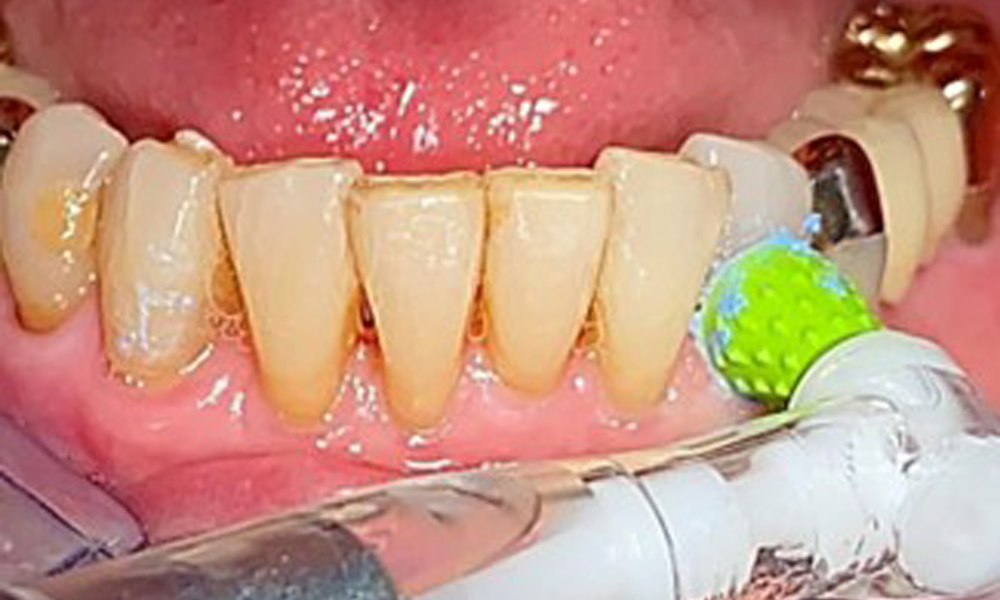

The patient was fitted with a combined removable maxillary telescopic prosthesis more than 25 years ago (Fig. 1, Fig. 2, Fig. 3) and is very happy with her dentures. The patient has an adequate fixed denture for the mandible (Fig. 4).

Frontal view with the maxillary denture in situ.

Fig. 1: Frontal view with the maxillary denture in situ.

The dental findings are as follows: Combined removable implant and tooth-supported telescopic prostheses on implants 15, 13, 21, 23, 24, 25 and tooth 11 (Fig. 1, Fig. 2, Fig. 3). The patient was fitted with a fixed mandibular denture. Adequate bridges were present over 37 to 34 and 45 to 47 (Fig. 4), the crown margins were intact and there were no active caries. A composite filling with a marginal gap was present on tooth 43. There was mandibular gingival recession, exposing 1 to 3 mm of root surface. This also applies to 11.

A single-tufted brush is specifically recommended for the telescopic prostheses (Fig. 8) and the patient should be advised on the appropriate interdental brush size (Fig. 9). The patient has been implementing these recommendations for intraoral hygiene at home for many years and was encouraged to continue during the professional preventive dental appointment.

Illustration of a single-tufted brush for home care of the implants and telescopic prostheses.

Fig. 8: Illustration of a single-tufted brush for home care of the implants and telescopic prostheses.